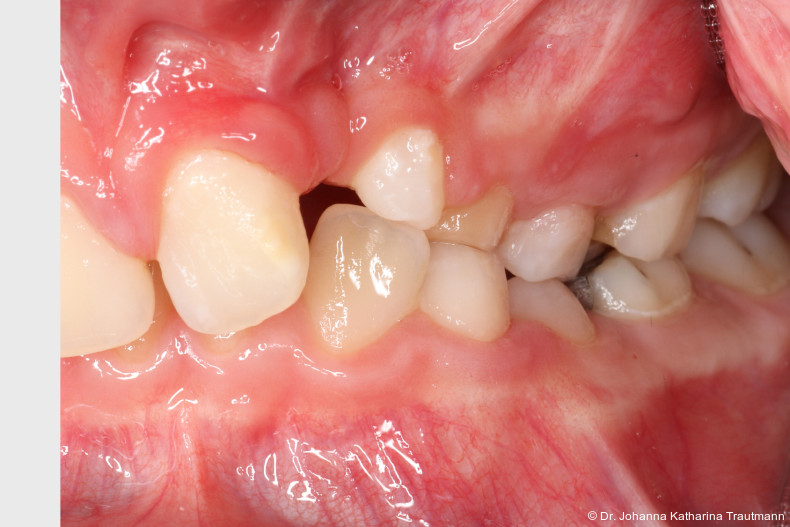

Zur genaueren Diagnostik der Lage beziehungen der Eckzähne und des Knochenangebotes im Spaltbereich kann neben den kieferorthopädi schen diagnostischen Unterlagen laut der S2 kLeitlinie Dentale digitale Volumentomografie6 auf eine dreidimensionale Bild gebung zurückgegriffen werden. In dieser zeigte sich eine vestibuläre Verlagerung des 13, eine palatinale Verlagerung des 23, sowie ein deutliches Knochendefizit im Spaltbereich mesial des hypoplastischen 22 (Abb. 2). Nach Auswertung der 3D-Daten erschien aufgrund der palatinalen Lage des 23 eine invasive Operation wie eine sekundäre Osteoplastik keinen entscheidenden Vorteil für die weitere Be handlung zu haben. In Rücksprache mit der Mund-Kiefer-Gesichtschirurgie der UMG wurde daher auf die OP verzichtet und initial die kieferorthopädische Therapie in den Vordergrund gestellt.